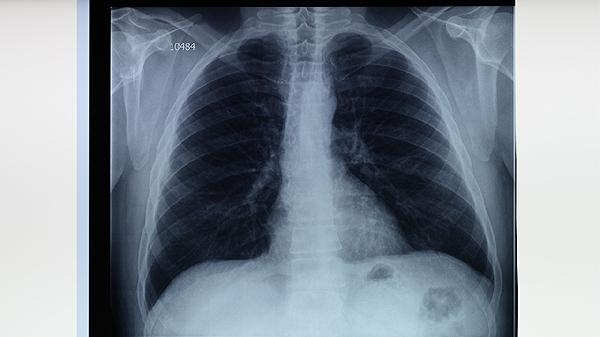

服用抗结核药物后皮肤变黑属于药物不良反应,可能与异烟肼、利福平等药物引起的色素沉着有关。皮肤颜色改变通常在停药后逐渐恢复,但需警惕药物过敏或肝肾功能异常等严重反应。

抗结核药物导致皮肤色素沉着的机制复杂,异烟肼可能通过干扰酪氨酸代谢影响黑色素合成,利福平则可能与胆红素代谢异常相关。部分患者用药2-3个月后出现面部、手掌等暴露部位肤色加深,通常呈均匀分布且无瘙痒疼痛。这种改变具有剂量依赖性,联合用药时更易发生。临床观察发现皮肤色素沉着在深肤色人群中更明显,但不会影响药物疗效。

少数患者可能出现严重的过敏反应,表现为皮肤快速变黑伴随皮疹、发热或黏膜损伤,需立即停药处理。长期大剂量使用吡嗪酰胺时,可能诱发光敏反应导致暴露部位色素沉着加重。个别病例报告显示,乙胺丁醇可引起指甲床色素改变。对于合并HIV感染的结核病患者,抗逆转录病毒药物与抗结核药的相互作用可能加剧皮肤不良反应。

建议用药期间做好防晒措施,避免紫外线直射加重色素沉着。定期监测肝功能及皮肤变化,若出现皮肤变黑伴随黄疸、尿色加深等症状需及时就医。停药后色素沉着多数在3-6个月消退,顽固性病例可咨询皮肤科医生进行局部治疗。保持均衡饮食并补充维生素B族,有助于减轻药物对皮肤的影响。